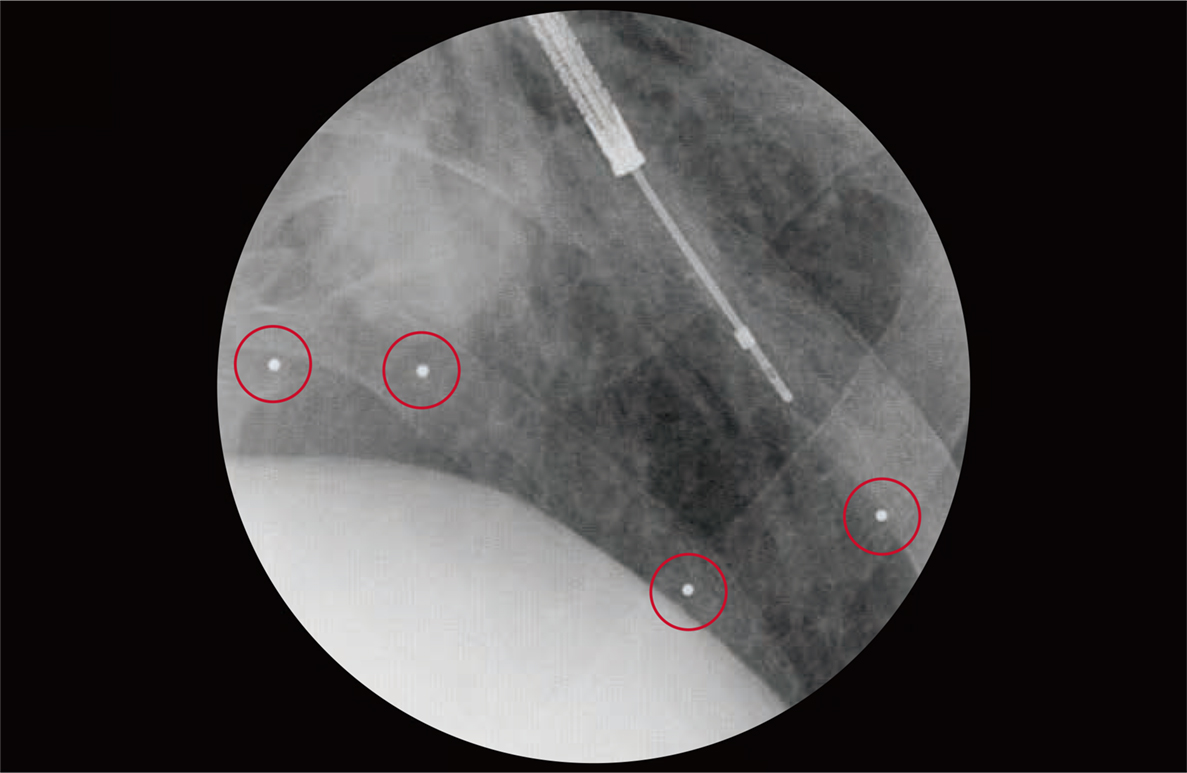

肺がんなど肺病変の位置確認精度向上に貢献

気管支鏡下で肺に留置できる位置確認用マーカー

- ・病変部近傍に留置することで、X線観察下での病変位置確認をサポートします。

- ・気管支内視鏡を用いて、病変部近傍の気管支に球体のマーカーを留置することができます。

セット内容:金マーカーカートリッジ(4個)、イントロデューサー